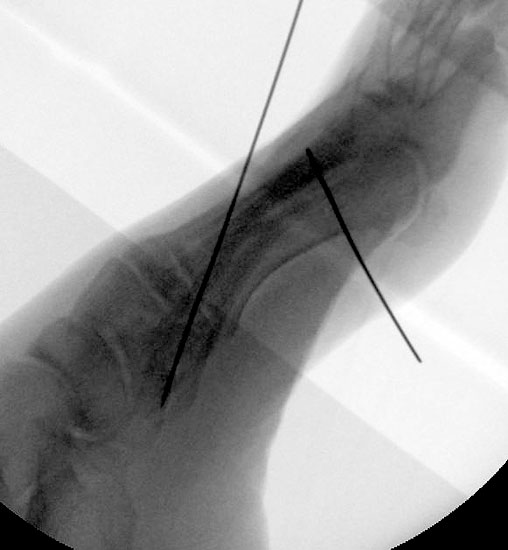

Röntgenaufnahme des Fußes im Stehen im dorsoplantaren und seitlichen Strahlengang (Abb. 1a-b).

Beurteilung des ersten Intermetatarsalwinkels (IMA), des Hallux valgus Winkels (HVA), des distalen (Distal Metatarsal Articular Angle, DMAA) und proximalen Gelenkflächenwinkels der Grundphalanx (Proximal Phalangeal Articular Angle, PPAA).

Abbildung 1a

Abbildung 1b